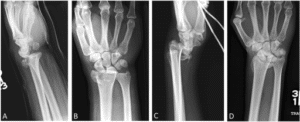

- K-wire fixation if…

- There is no intra-articular involvement OR

- Displacement of radial-carpel joint can be reduced under closed manipulation (2).

- Open reduction and internal fixation (ORIF) if…

- Reduction of the joint surface is not possible under closed manipulation (2).